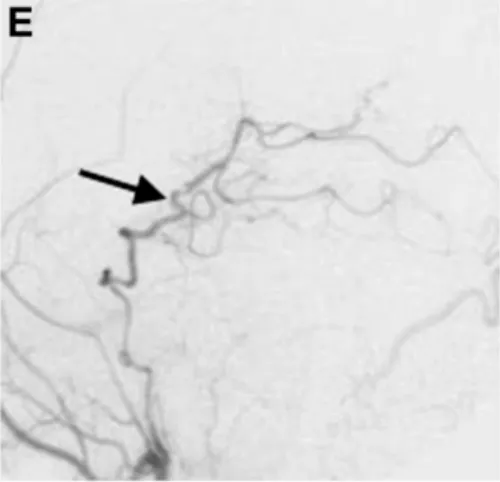

术后1周复查颈外动脉血管造影显示,通过新建的分流血管,左侧大脑后动脉供血区血流完全通畅(图E箭头标注),没有出现任何缺血迹象。

术后1周颈外动脉血管造影显示,通过分流血管,整个左侧大脑后动脉供血区血流良好(箭头标注)。